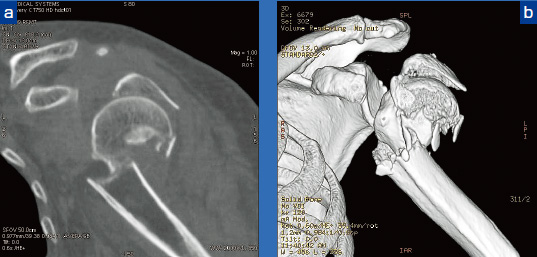

肩関節病変、上腕骨骨折、股関節、腕おろし体幹部撮影など、ストリークアーチファクトの発生しやすい条件下において、HDCTはアーチファクトの影響が軽減され、画質が向上し、有用性のある装置であることが確認できた。図6、7に、HDCTが有用であった症例画像を提示する。

図6 上腕骨頭骨折症例 a:MPR冠状断像 b:VR像